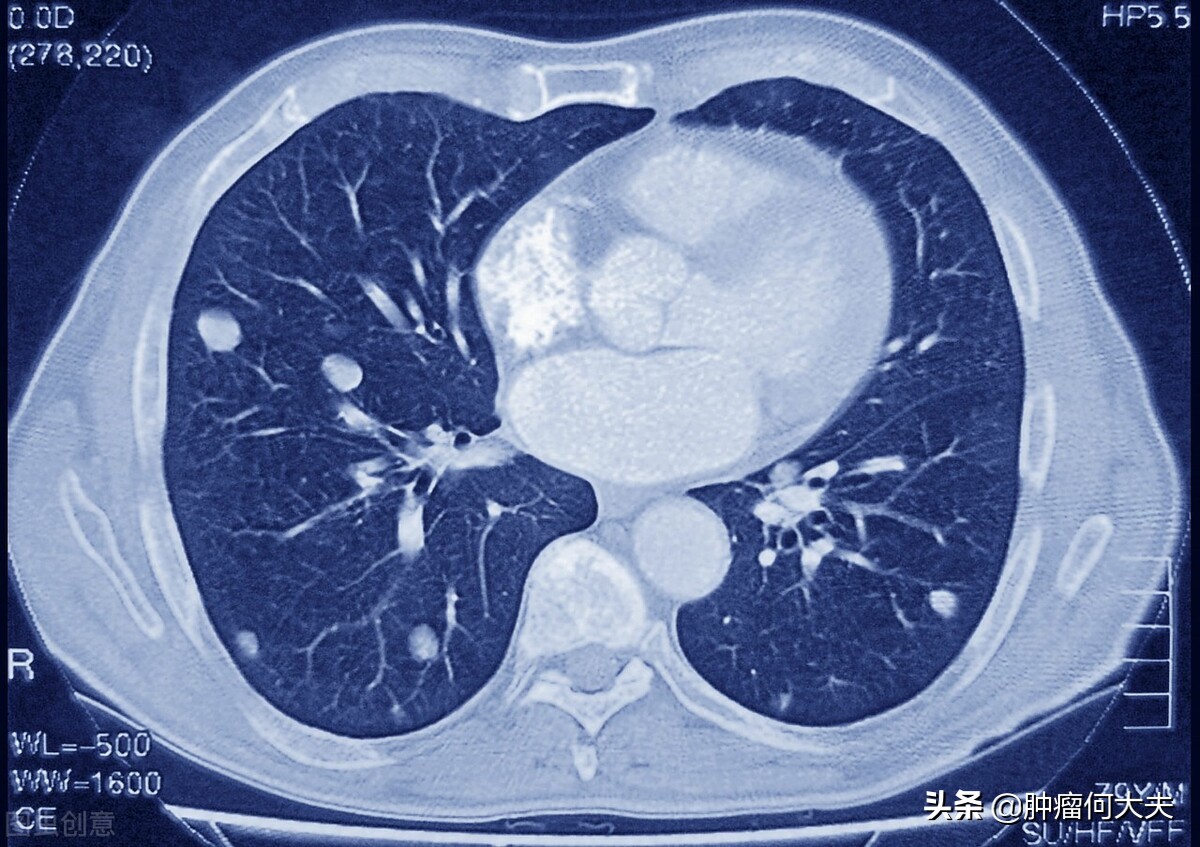

第一,肺转移。临床上肺癌本身,乳腺癌、卵巢癌、食管癌、胃癌、结直肠癌、肝癌、骨肉瘤以及甲状腺癌等比较容易发生肺转移。出现肺转移会怎么样?孤立单个的肺转移,特殊肿瘤出现了肺转移,合理治疗也能够获得治愈的机会。所以并不是一旦肺转移,人就注定没救了,继而放弃所有治疗;

肺转移